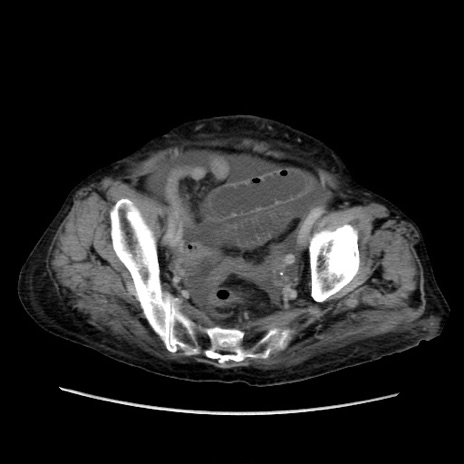

症例31(横断像)

【症例】80歳代 女性

【主訴】腹部膨満感

【現病歴】他院にて肝硬変にてフォロー中。1週間前から便秘、腹部膨満感、臍部腫瘤あり受診となる。

【既往歴】肝硬変

【身体所見】腹部膨隆あり、皮膚変化なし、疼痛なし。

【データ】WBC 4600、CRP 0.25